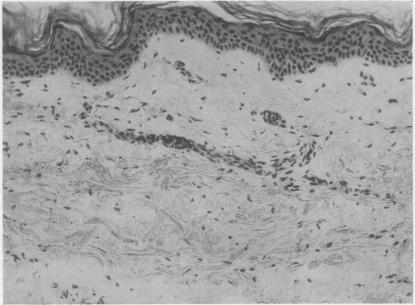

Erythema annulare in adults with acute rheumatism.

Ann Rheum Dis. 1962 Mar;21(1):59-62. doi: 10.1136/ard.21.1.59.